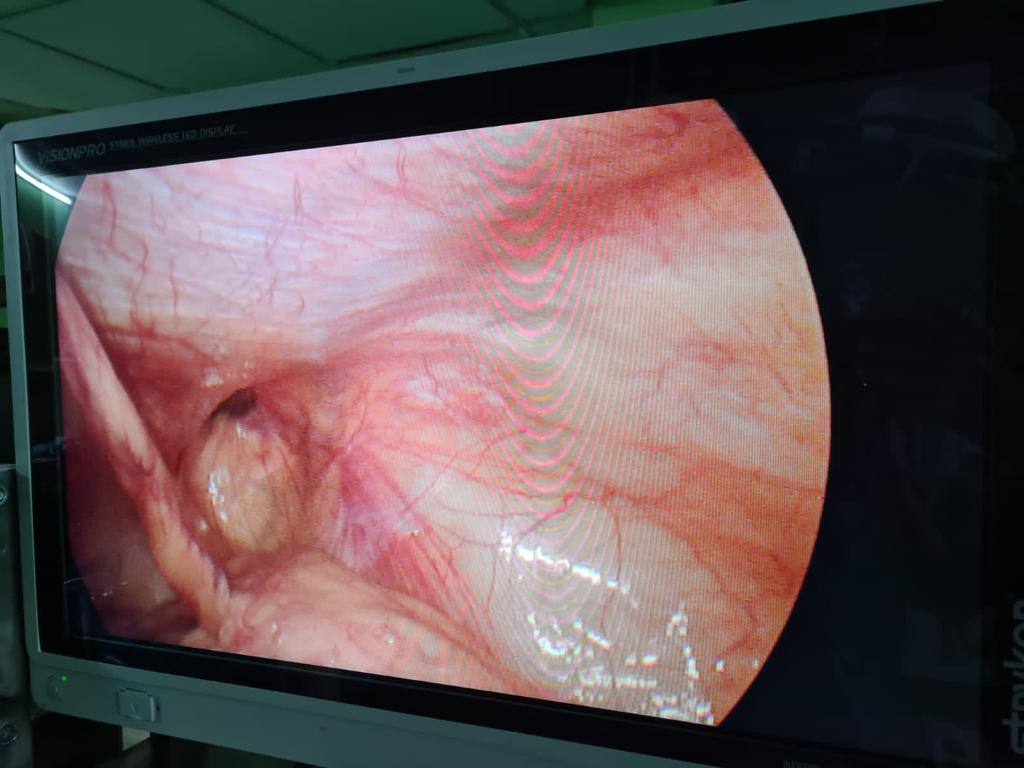

Difficult retrocecal appendix completely done laparoscopically

Difficult cases of appendicitis done completely laparoscopically